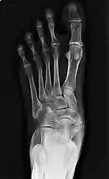

![]() X-ray of the foot showing an accessory navicular bone | |

From left to right: Type 1, 2 and 3